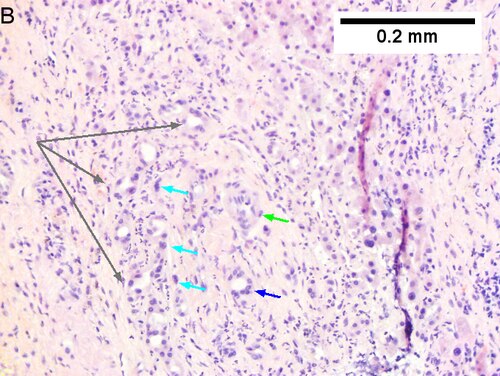

Cholangiocarcinoma, intrahepatic, small duct type. Middle aged man with jaundice. Small dark tumorous masses [arrows] irrupt scar (Row 1 Left 20X). Cribriforming (net like pattern) of gland in gland [arrow] without intervening stroma, which can be difficult to discern from reactive bile ducts at times (Row 1 Right 100X). A second focus shows, on the left, glands with disorderly spread, further explored, and in the middle, partly formed glands with necrosis, further explored, both diagnostic (Row 2 Left 100X). Note how some glands go up and down [red arrows] & others go right to left [black arrows] showing disorderly spread (Row 2 Right 400X). Note necrotic cell nuclei [red arrows] and incompletely formed glands [black arrows] (Row 4 Left 200X). Nuclear anaplasia is also able to be used for a definite diagnosis, but there is considerable nuclear variability in reactive bile duct proliferations, making it less facile than disorderly spread, incomplete glands, and necrotic nuclei (Row 3 Right 400X).